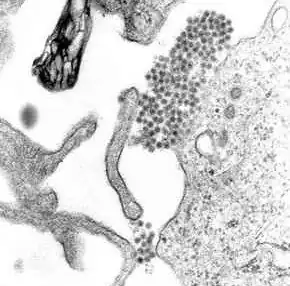

Eenmaal in de huid gedrongen, hecht het dengue-virus zich aan de Langerhanscellen (dendritische cellen in de huid die pathogenen opsporen).[25] Het virus dringt de cellen binnen doordat viruseiwitten zich hechten aan membraaneiwitten op de cellen van Langerhans, met name het type C-lectine dat DC-SIGN heet, mannose-receptoren en CLEC5A.[13] DC-SIGN, een aspecifieke receptor voor lichaamsvreemde stoffen op dendritische cellen, lijkt de voornaamste toegangsweg te zijn.[15] De dendritische cel begeeft zich naar de dichtstbijzijnde lymfeklier. Ondertussen wordt het genoom van het virus gekopieerd in de aan het membraan gebonden blaasjes op het endoplasmatisch reticulum van de cel, waar het eiwitsynthese-mechanisme van de cel nieuwe viruseiwitten produceert en het virale RNA wordt gekopieerd. De onvolgroeide virusdeeltjes worden vervoerd naar het Golgiapparaat, dat deel van de cel waar sommige eiwitten de benodigde suikerketens (glycoproteïne) krijgen. De inmiddels volgroeide nieuwe virussen ontkiemen op het oppervlak van de geïnfecteerde cel en worden afgescheiden door middel van exocytose. Vervolgens kunnen ze andere witte bloedcellen binnendringen, zoals monocyten en macrofagen.[13]